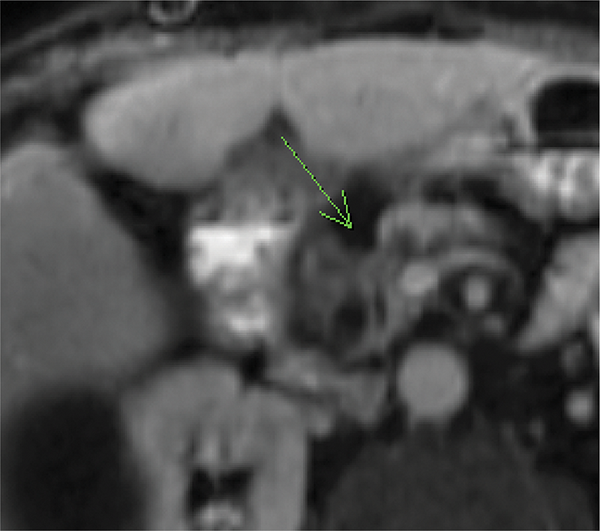

Figure 1

Axial fat‑suppressed contrast‑enhanced T1‑WI shows an ill‑defined hypovascular pancreatic head mass (arrow) with dilatation of the CBD and pancreatic duct. The suspected diagnosis was PDAC.